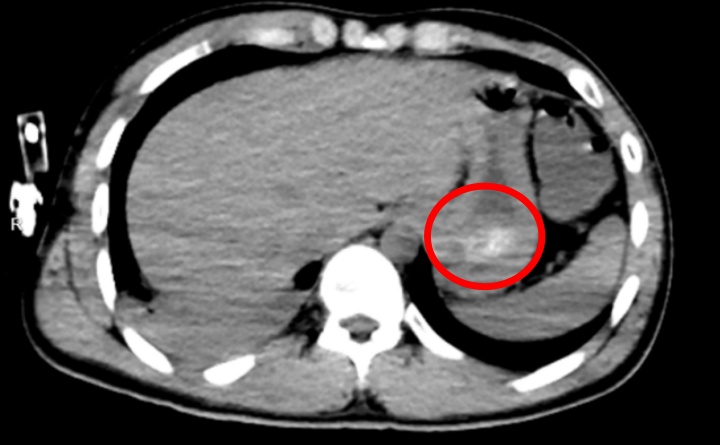

全腹CT结果验证这一判断:他的胃底可见大量团块状高密度影,正是那团凝结的药物;同时,胸部CT也提示,双肺出现渗出性病变,右肺下叶尤为严重,已经出现了吸入性肺炎。

也就是说,导致林先生昏迷不醒的——正是胃里还在持续释放毒性的药团,再叠加吸入性肺炎。